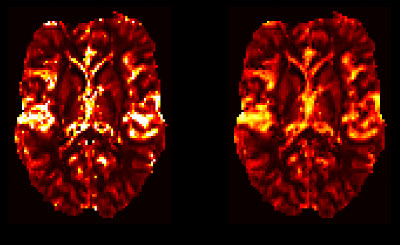

Vascular Model Based Perfusion Quantification for DSC-MRI (VERBENA) is a Bayesian Inference tool for quantification of perfusion and other haemodynamic parameters from Dynamic Susceptibility Contrast perfusion MRI of the brain. VERBENA complements the BASIL tools for the quantification of perfusion using Arterial Spin Labelling MRI and is built on the same core inference algorithm (FABBER). VERBENA uses a specific physiological model for capillary transit of contrast within the blood generally termed the 'vascular model' that was first described by Ostergaard et al. (1999). In VERBENA the model has been extended to explicitly infer the mean transit time and also to optionally include correction for macro vascular contamination - contrast agent within arterial vessels - more information on the model can be found in the theory section.

This would process the 4D DSC data in data.nii.gz using the AIFs supplied in aif.nii.gz using the modified Vascular Model to estimate (relative) perfusion, commonly referred to as cerebral blood flow (rCBF), along with the mean transit time (MTT) and the transit time distribution parameter lambda; maps of which are placed in the output directory. Analysis is only performed within the mask supplied (mask.nii.gz) which will normally have been derived from a brain extraction using BET or other equivalent tool.

In the context of DSC-MRI the convolution model is applied to each voxel in turn and the residue function represents the residence of the agent within the tissue volume described by the voxel. In the healthy brain the Gadolinium tracer that is used in DSC-MRI does not leave the vasculature and thus the residue function encapsulates the transit of the contrast agent through the capillary bed. In fact the residue function is the integral of the distribution of transit times for blood passing through the voxel - a key parameter of which is the mean transit time (MTT), which is routinely used in DSC perfusion as a surrogate measure of perfusion (although it is often calculated without finding the transit distribution itself).